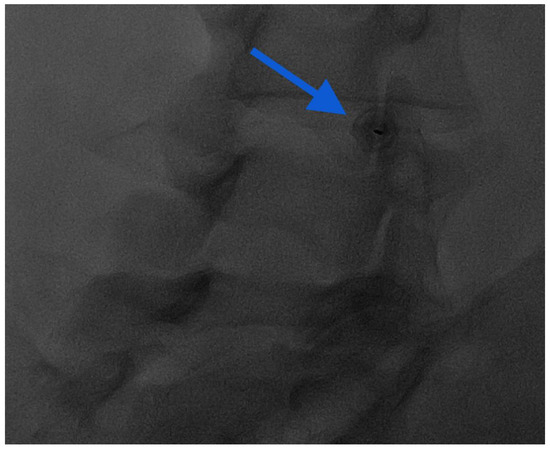

- Napoli, A.; Alfieri, G.; De Maio, A.; Panella, E.; Scipione, R.; Facchini, G.; Albisinni, U.; Spinnato, P.; Nardis, P.G.; Tramutoli, R.; et al. CT-Guided Pulsed Radiofrequency Combined with Steroid Injection for Sciatica from Herniated Disk: A Randomized Trial. Radiology 2023, 307, e221478. [Google Scholar] [CrossRef] [PubMed]

- Amoretti, N.; Amoretti, M.-E.; Hovorka, I.; Hauger, O.; Boileau, P.; Huwart, L. Percutaneous Facet Screw Fixation of Lumbar Spine with CT and Fluoroscopic Guidance: A Feasibility Study. Radiology 2013, 268, 548–555. [Google Scholar] [CrossRef]